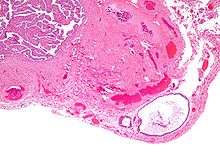

High magnification micrograph of a Brenner tumor showing the characteristic coffee bean nuclei which are also seen in Walthard cell rests. H&E stain.

They appear as white/yellow cysts or nodules that can reach a size of 2 millimeters. They typically have elliptical nuclei with a long groove (along the major axis) - so called - "coffee bean" nuclei.

It has been suggested that these cell rests are the histogenetic origins of Brenner tumors, due to the histological similarity of the epithelium of Walthard cell rests and Brenner tumors to the urothelium of the lower urinary tract. Also, it has been proposed that Brenner tumors and Walthard cell rests signify urothelial differentiation within the female genital tract.